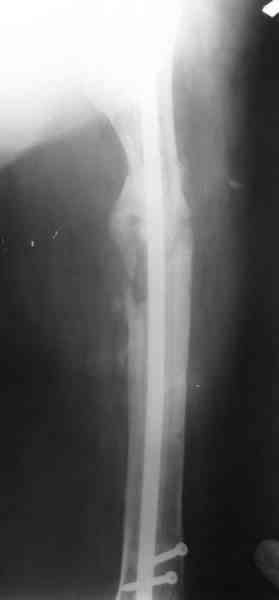

В настоящее время наш пациент ( см. http://weborto.net/forum/1177351385/) ходит с одним костылем. У него периодически открывается свищ на задне-наружной поверхности бедра с умеренным серозно-гнойным отделяемым. Температура тела и анализы нормальные. На рентгенограммах имеются признаки консолидации ложного сустава.

1, 2, 3, 4 - рентгенограммы бедра от 8 августа этого года (через четыре месяца после операции);